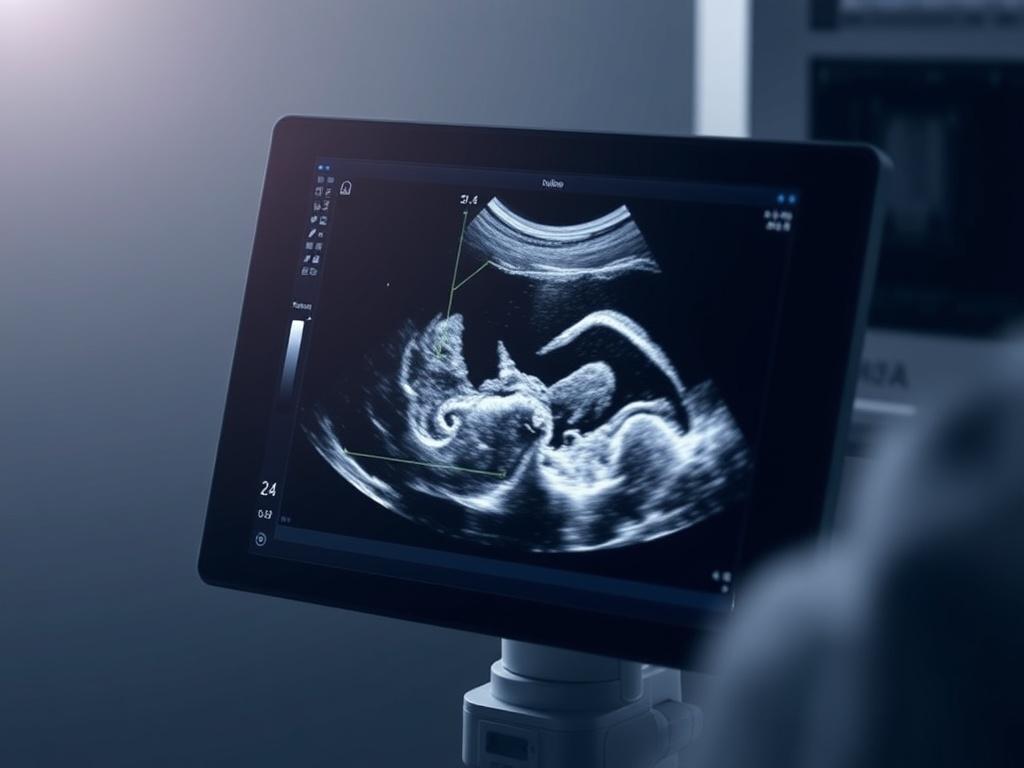

| Обследование беременности | Плод, плацента, количество околоплодной жидкости | Обычно без специальной подготовки для поздних сроков | Безопасность, наблюдение за развитием плода |

Если проводится трансвагинальное или трансректальное исследование, врач объяснит ход процедуры и проведёт её кратко и аккуратно. В таких случаях используют специальные датчики в стерильных чехлах, чтобы уменьшить дискомфорт. Во время исследований беременности часто показывают изображение на мониторе и объясняют, что видно.